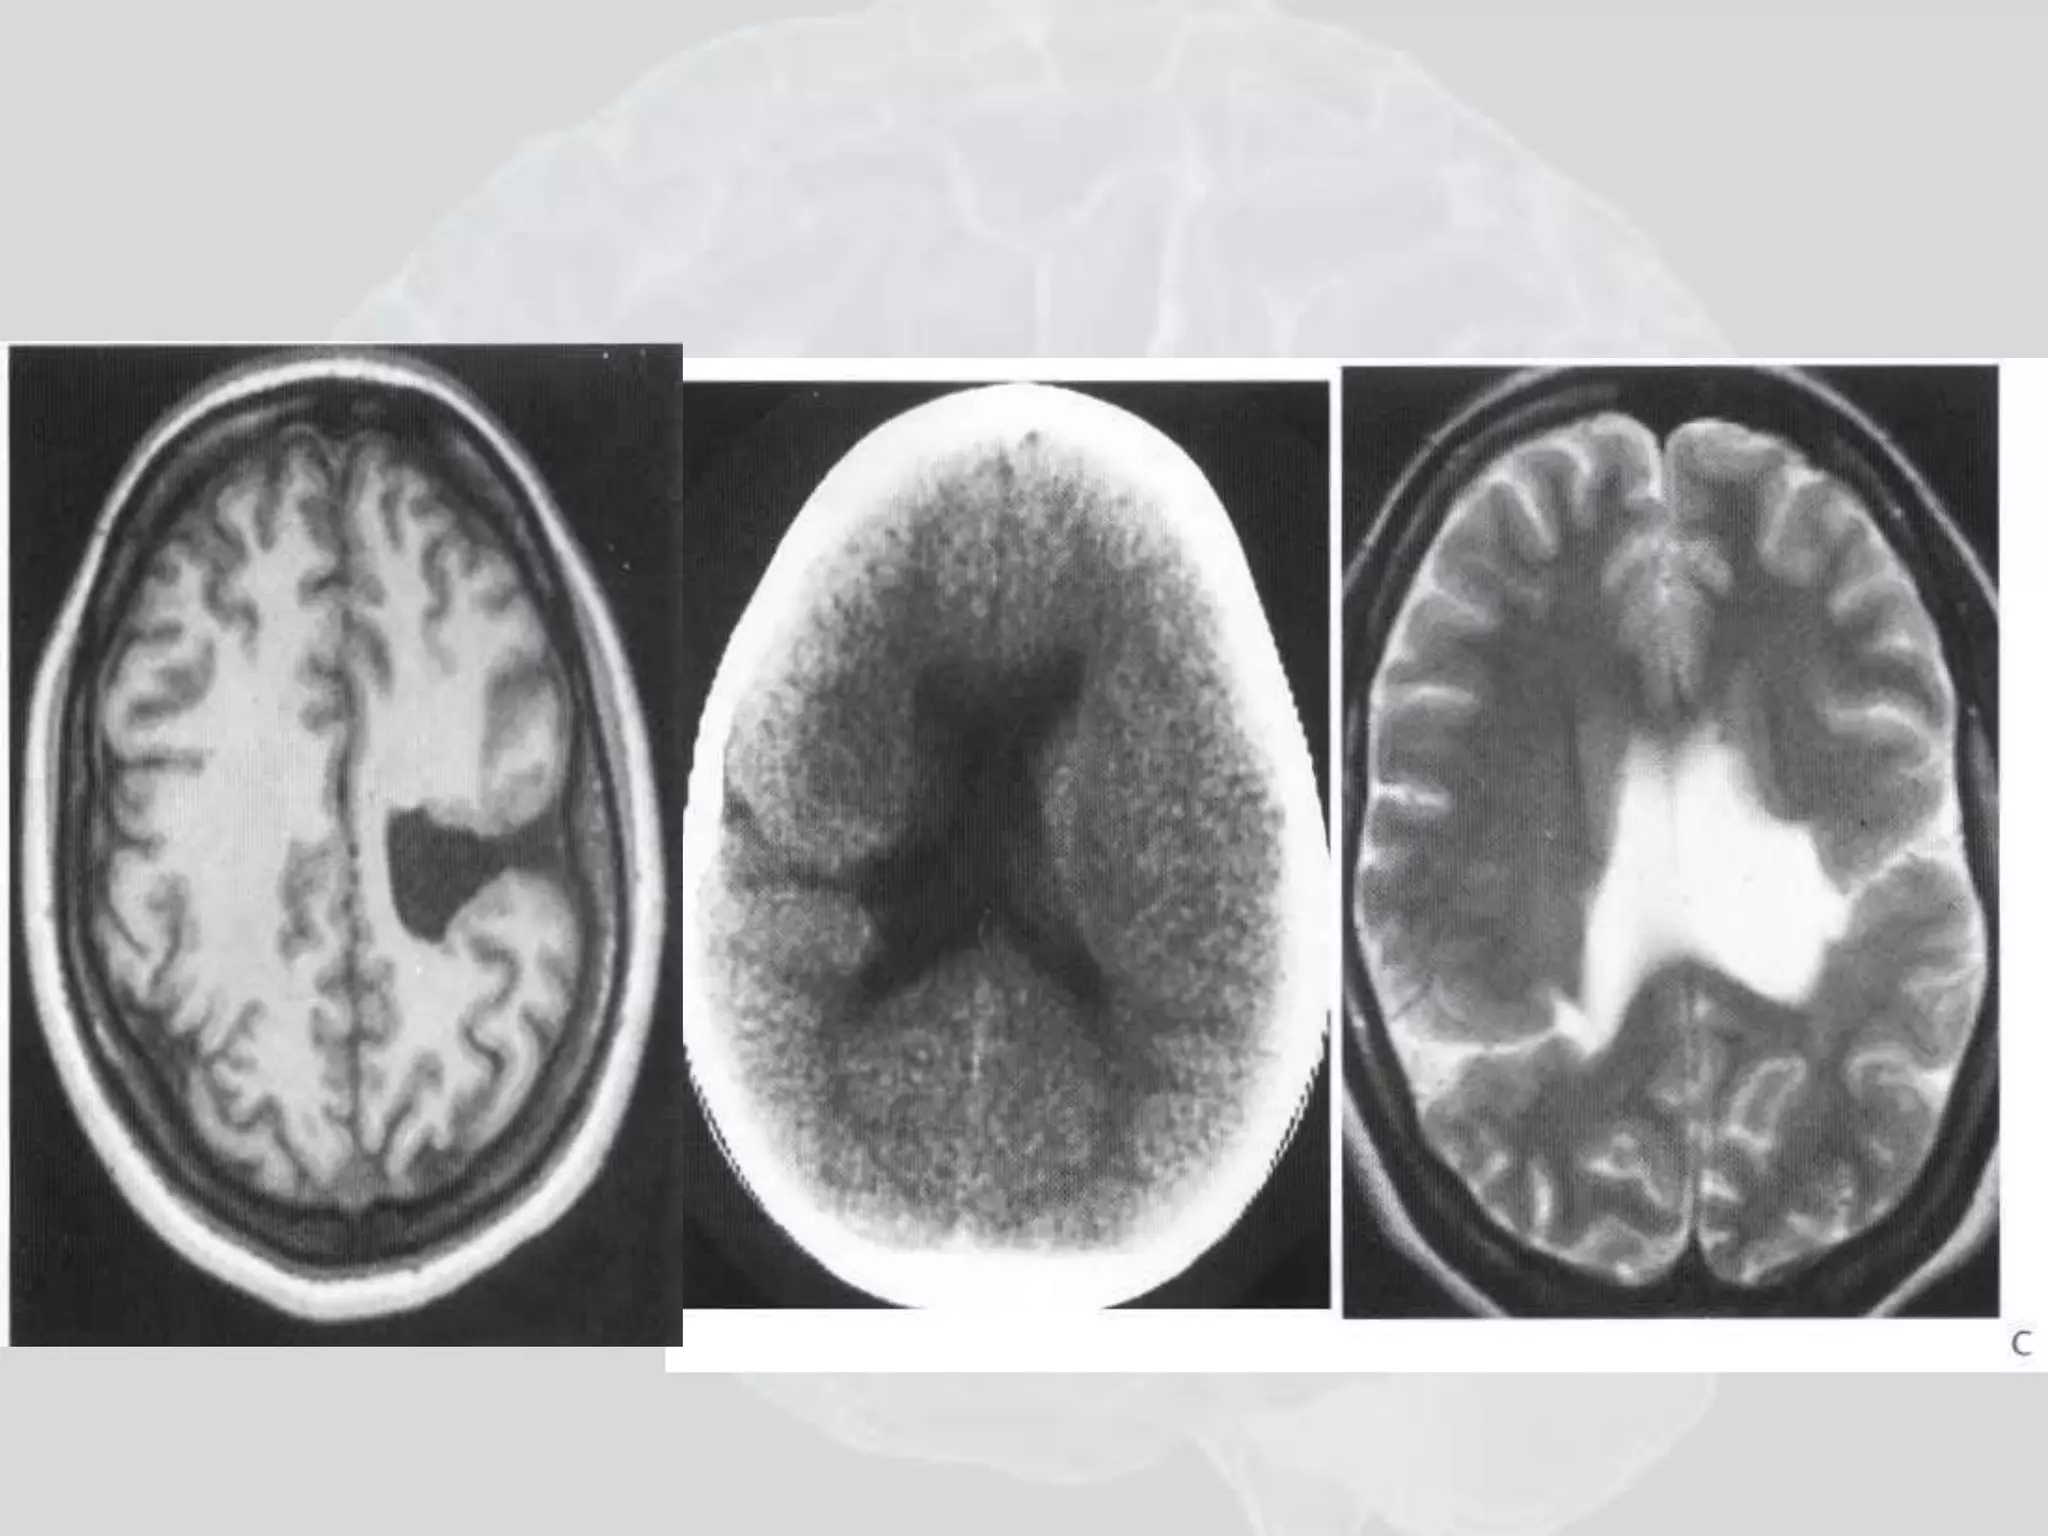

Stroke

MCA Stroke

“Dense MCA”

Case 2

Epidural

heamotoma

Subarachnoid heamorrhage

Subarachnoid Hemorrhage

Blood shows white on CT.

Anterior Communicating Artery

aneurysm has burst, flooding the

basal structures under the brain

outside the brain parenchyma, but

will occasionally empty into a

Ventricle as it has on the left here

(see fluid level). Note typical

• 110.

• 111.

• 112.

• 113.

• 114.

Subarachnoid Hemorrhage Bloodshows white on CT. Anterior Communicating Artery aneurysm has burst, flooding the basal structures under the brain outside the brain parenchyma, but will occasionally empty into a Ventricle as it has on the left here (see fluid level). Note typical “bat wing” shape just above the mid-brain (green arrow).